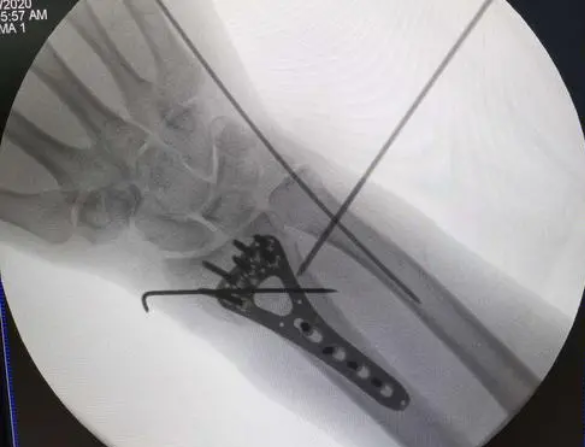

2.1 经皮克氏针闭合复位术 经皮克氏针闭合复位属于微创手术的重要方式,这一手术方式适合不稳定性关节外骨折伴有背侧移位的患者疾病治疗,且其能够成为石膏外固定和外固定支架的辅助方式的情况下促使患者疾病治疗的效果更加显著。在手法复位石膏外固定治疗的基础上其本身也存在着再次位移的风险情况,而这一情况下,如果经皮克氏针固定断端骨折块也就充分防止发生复位后骨折再次移位的现象,但是经皮克氏针所可以充分承受的负荷也会较小,因此其可以充分维持和支撑干骺端粉碎骨折的能力明显不足。此外,经皮克氏针还可以导致针道感染和Brodie脓肿等并发症疾病。

闭合复位经皮克氏针微创髓内固定手术在实施桡骨远端干骺交界区骨折治疗的时候,其本身和切开复位外支架固定术的效果比较相似,且并发症发生几率较低,能够充分减少患者损伤发生率,使得患者骨折得以有效愈合。

桡骨远端C型骨折采用闭合复位经皮克氏针固定治疗的方式存在着比较显著的效果,骨折治疗效果也比较显著,桡骨远端C型骨折利用闭合复位经皮克氏针固定的方式实施治疗,可以促使患者的骨折疾病更快痊愈。

闭合复位经皮克氏针内固定治疗桡骨远端不稳定骨骺骨折疾病的时候,利用闭合复位克氏针内固定治疗效果比较显著,且不会发生感染的现象,可作为不稳定骨骺骨折治疗的主要方式。

闭合复位经皮克氏针的方式实施儿童桡骨远端骨折疾病治疗存在着操作较为简单的特点,且对患者造成的创伤不明显,值得临床应用推广。